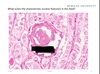

Thyroid tissue

A

Thyroid tissue ;

Define the symbol and identify the stain used